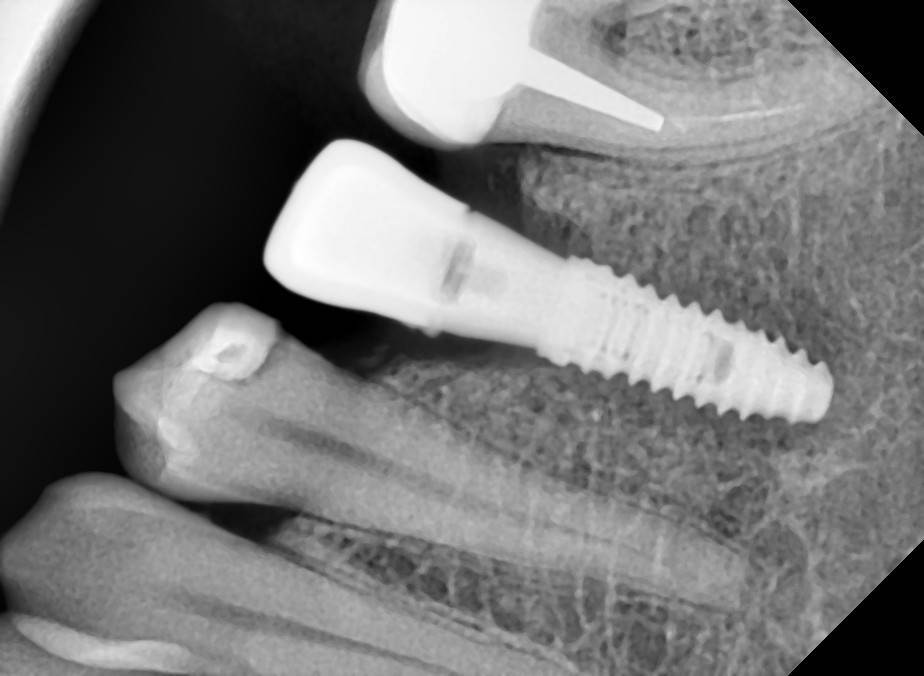

Fin Опубликовано 23 мая, 2022 Поделиться Опубликовано 23 мая, 2022 19 часов назад, Женька сказал: на суперлайнах вообще почти не падает от такой игры) да, это уже знаю) научен горьким опытом резорбции на 2-3 витка) В потому что основной торк у Вас на шейке импланта в таких случаях возникает. В Моей практике Шаг назад и два вперед работает и в кортикальной ткани если очень долго это делать.Например если получаю гиперторк на последнем мм, не убираю имплант а продолжаю рабоать с другим и возвращаюсь к нему через 2-3 минуты (шаг назад и два вперед) потом снова и снова. Можно пройти метчиком кортикальную ткань или следующим размером сверла. Кость над платформой можно убрать бон профайлером если его нет, беру приямой наконечник с двердосплавным бором 200-300 об с макс охлаждением. От себя советую всегда делать снимки после установки формиков (и на ВЧ и на НЧ) часто в кость упираются а мы думаем что прикрутили. 19 часов назад, Aquarius сказал: Собственными глазами видел на собственном винте не то что восстановление резорбции в 3 витка после гиперторка , но и гиперрост кости после 3-х летней функции. Вот и пойми эти импланты. Линкявичуса читаю, чтобы понять По поводу восстановления кости. Импланты поставлены около 6 лет назад. Конечно я понимаю что сейчас допустил много ошибок ,но вот у платформы 3.5 кость даже наросла. И второй случай, не такой показательный конечно, но факт. 1 снимок на момент примерки каркаса, мерял с другой стороны мостик и заодно примерил и эту коронку Ссылка на комментарий

Aquarius Опубликовано 27 мая, 2022 Поделиться Опубликовано 27 мая, 2022 (изменено) 2016 г - установка имплантов. В то время находился под впечатлением от исследований Карлоса по гиперторку. Дал под сотню на дистальном импланте . Потом сильно пожалел))) Второй снимок - спустя 4 года на осмотре. https://wampi.ru/image/RZ3XaNg https://wampi.ru/image/RZ3XLcn Изменено 27 мая, 2022 пользователем Aquarius Ссылка на комментарий